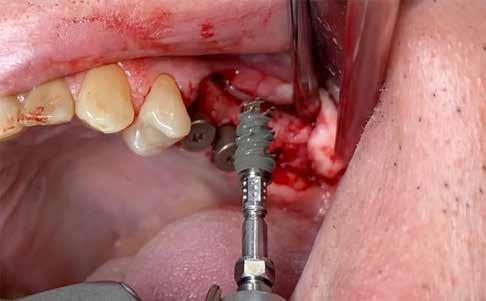

A nyomtatott guide in-situ. A szükséges interokkluzális helyigényt a fúrót bepróbálva ellenőriztük.

A guide stabilitását először a mintán, majd szájban ellenőriztem, illetve az 1 mm-es pilot fúró (Meisinger pilot implantátum fúró – Hager & Meisinger, Neuss, Németország) dimenzióstabilitását is kontrolláltam (3., 4. ábra)

A fúrás kezdőpontját a fúróperselyen keresztül vékony gyémántfúróval jelöltem a zománcon. A jelölőfúró átmérőjének – a persely megóvása érdekében – 1 mm-nél keskenyebbnek kell lennie. Ezután szabad kézzel átfúrtam a zománcot (5. ábra).

A dentint ismét a guide segítségével preparáltam (EndoExplorer EX1 – Ko-

met Dental). A megfelelő hűtés érdekében a fúrást 1-2 mm-enként megszakítottam, a fúrót megtisztítottam és az üreget sóoldattal átöblítettem. A tervezett mélység elérése után a fúróvezetőt eltávolítottam és abszolút izolálást helyeztem fel, melyet folyékony kofferdammal tökéletesítettem (Ultradent Products). A gyökércsatornát a fúró hegyéhez képest oldalirányban leltem fel (6-7. ábra)